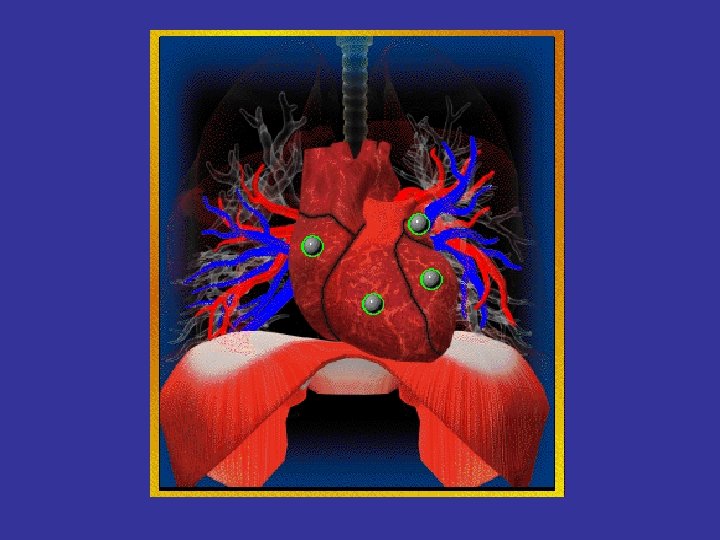

* trachea ; position & caliber * hila : lymphadenopathy * mediastinum contour : ? mass * heart : cardiac configuration Mediastinum, heart and hila

How to read a chest x ray ? • 1 - chest wall, bones and abdomen * bones; lesions or fractures * soft tissue ; mastectomy or soft tissue tumors • 2 - heart and mediastinum * trachea ; position & caliber * hila : lymphadenopathy * mediastinum contour : ? mass * heart : cardiac configuration • 3 - lungs opacity or lucency